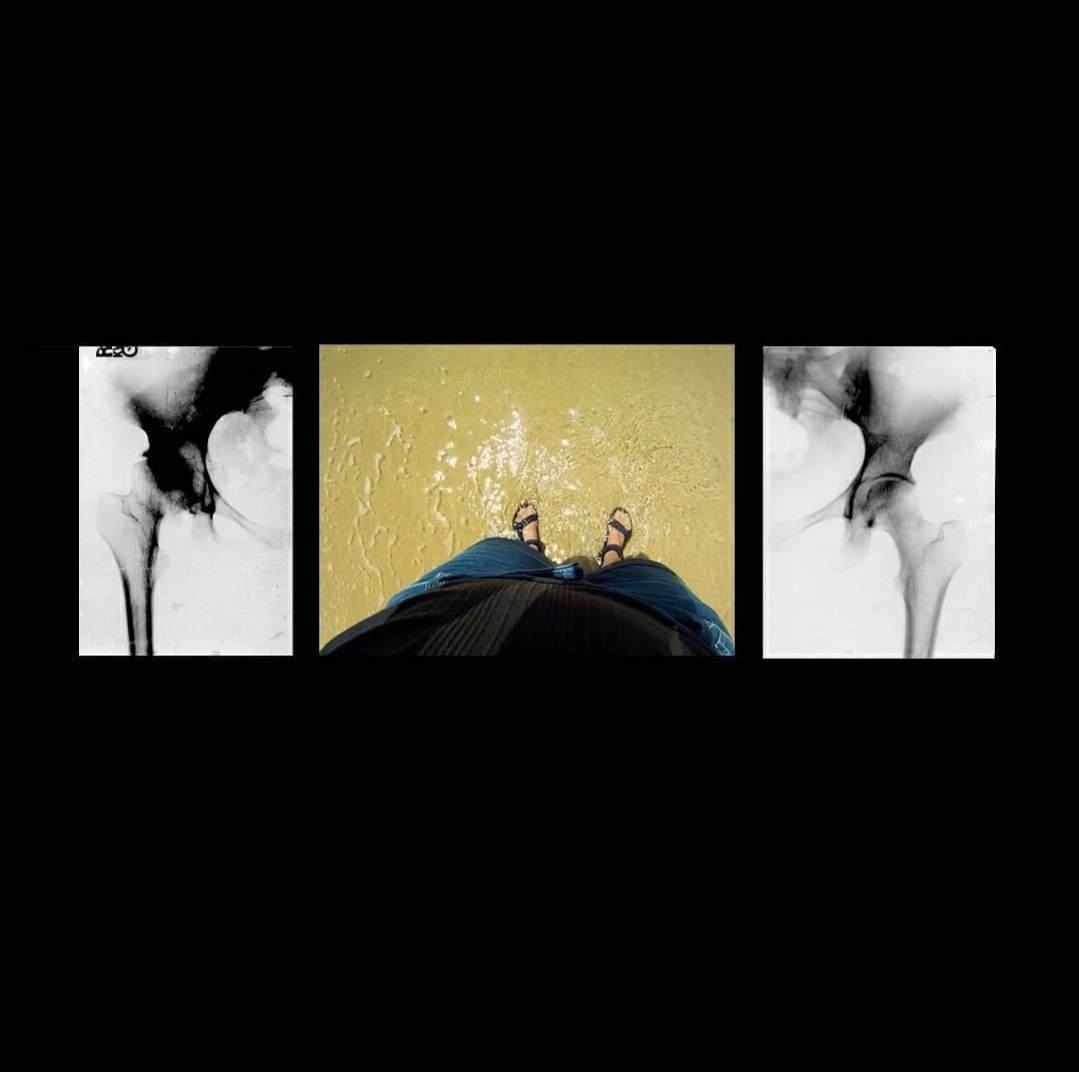

베토벤이 그의 장애를 포용하면서 중기 또는 영웅시기에 했던 작곡은 클래식 음악에 혁명을 일으켰습니다. 베토벤의 두려움과 자기 고립은 저또한 깊이 이해하는 경험입니다. 맨 처음 이동성 장애가 있다는 진단을 받았을 때 (추후 자가면역질환으로 인한 것임을 알게 되었습니다) 저는 장애를 숨기고 몸이 다르게 움직이는 것에 대한 수치심을 내면화하는 데 수년을 보냈습니다. 이것은 또한 저를 고립되게 만들었습니다. 시간이 지남에 따라 예술을 통해 저의 고유함에 자부심을 갖는 법을 배웠습니다. 이 작품의 영상은 2011년 촬영한 것으로 제가 고관절 치환 수술 전후 79 일 동안 걷는 모습입니다. 79일의 촬영분 중 8개의 동영상을 저의 장애를 드러내는 첫 전시회에 공개하였습니다.